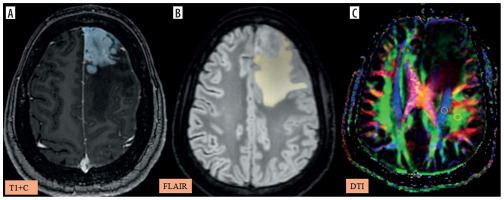

Figure 6

A-C) Patient with metastasis in the left frontal region presenting with right lower limb weakness and disorientation. A) Axial post-contrast T1 image shows the segmented tumour volume (blue). B) Axial fluid-attenuated inversion recovery (FLAIR) image shows the segmented peritumoral oedema (yellow). C) Image describing the calculation of the diffusion tensor image analysis along the perivascular space (DTI-ALPS) index using two regions of interest (ROIs) drawn within the projection (blue) and association (green) fibres in the left periventricular region